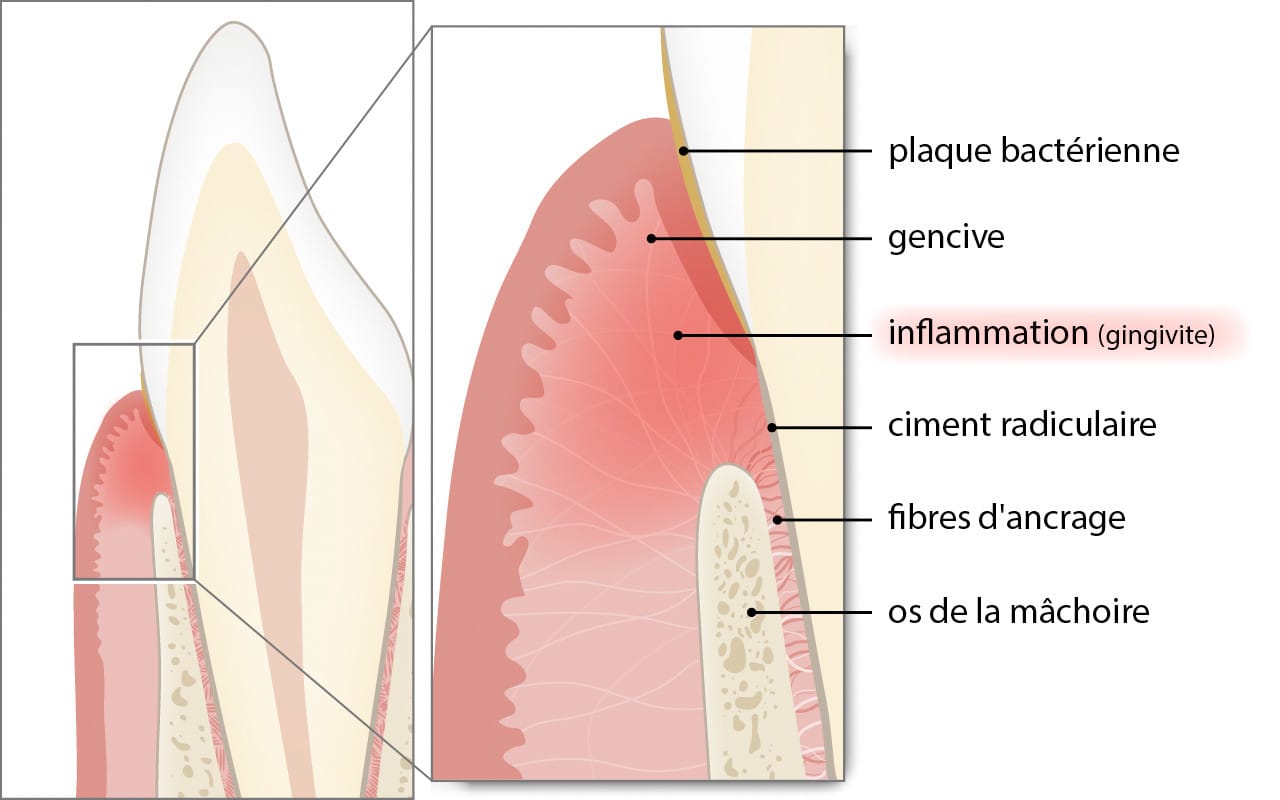

La parodontite est une maladie inflammatoire chronique qui atteint les tissus maintenant les dents dans l’os.

Elle débute généralement par une gingivite (inflammation superficielle de la gencive) provoquée par la plaque bactérienne.

Le parodonte comprend :

La gencive

Le ligament parodontal (fibres d’ancrage)

Le cément (surface de la racine)

L’os de la mâchoire

Lorsque ces structures sont atteintes, la dent perd progressivement son ancrage.